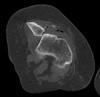

Fratura do platô tibial lateral - Schatzker tipo 2 (traço de fratura + depressão do plato lateral).